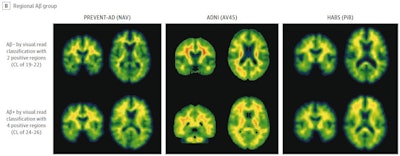

The researchers analyzed imaging from 817 older adults from three different cohorts (mean ages of 63.5, 73.6, and 73.7) used to compare amyloid-negative patients and patients diagnosed with the disease. They compared patients who were truly negative for Alzheimer's disease with patients who showed early signs of PET radiotracer binding to amyloid in seven brain areas known to be associated with the disease.

Importantly, all patients would have been considered negative at the time of their clinical trial participation, based on thresholds for visual interpretations of amyloid PET scans built into the trial's protocol, the authors wrote.

Ultimately, one of the most common approaches in clinical trials is to analyze amyloid PET scans and classify individuals into negative and positive groups based on visual reads. But this approach may not always be optimal for identifying individuals with early abnormal amyloid levels, the authors suggest.